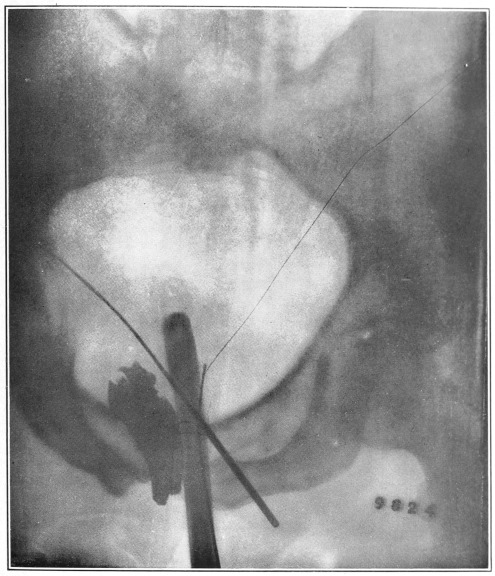

Nine Radiograph Illustrations Showing Mucus Channels and Cavities200

Rebellion of our outraged Internal Economy.